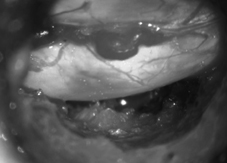

* 微創腰椎間盤突出切除手術:使用各式微創手術套管,於顯微鏡或內視鏡輔助下進行腰椎間盤突出切除手術,與前述手術具有相同治療效果,且可將手術傷口進一步縮小至兩公分以下,是目前治療腰椎間盤突出症的主流手術。

微創腰椎間盤突出切除手術